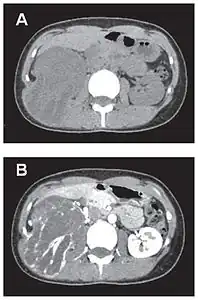

- Tumeur fibreuse solitaire du rétropéritoine

Aspect tomodensitométrique, sans (A) puis avec (B) injection de produit de contraste[44].

En tomodensitométrie[20],[31], quelle que soit la localisation, une tumeur fibreuse solitaire apparaît comme une masse tissulaire ovoïde ou lobulée, bien délimitée, refoulant les structures voisines sans les envahir. Elle se rehausse fortement après injection de produit de contraste. Les tumeurs de petite taille sont homogènes, mais les plus volumineuses présentent des plages hétérogènes de nécrose et d'hémorragie intra-tumorale. Il n'y a pas habituellement de calcifications et, lorsqu'elles sont présentes, elles sont de petite taille[31]. Les tumeurs malignes peuvent se présenter accompagnées de nodules pulmonaires métastatiques, et tendent à être plus volumineuses et plus hétérogènes[42].